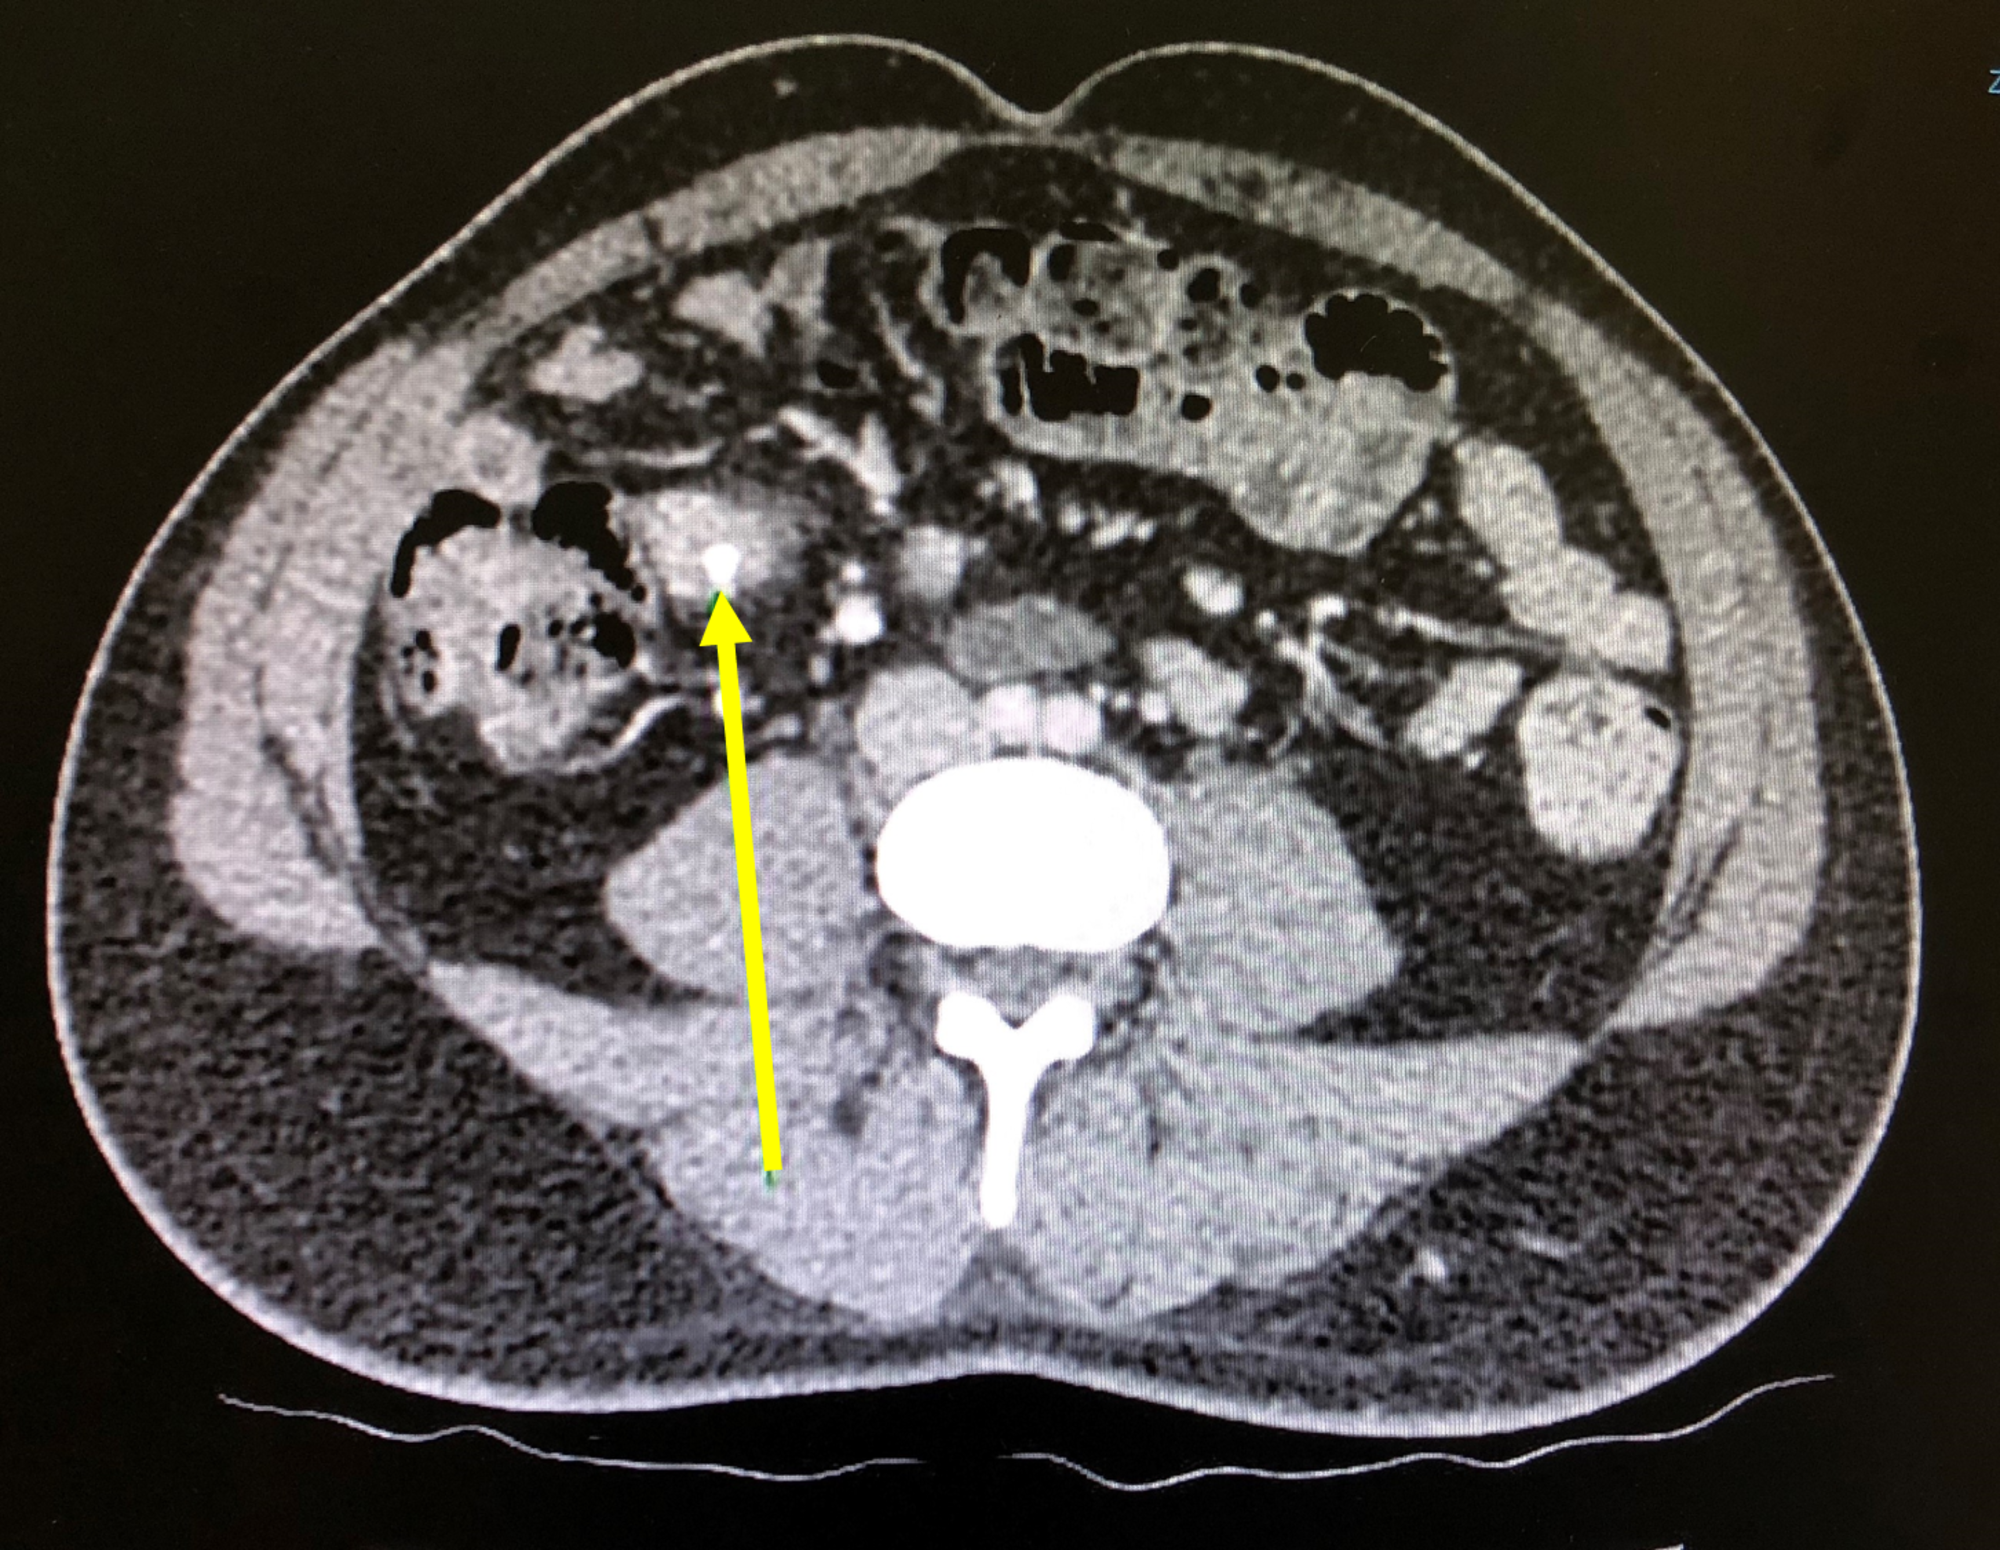

Ischemic colitis in a critically ill patient. CT scan obtained with Ischemic Colitis Perforation Ischemic colitis is a leading cause of acute abdomen in elderly patients. Chronic forms usually present as chronic segmental colitis and may result in stricture formation. Ischaemic colitis occurs when there is an acute, transient compromise in blood flow, below that required for the metabolic needs of the colon. Ischemic colitis usually gets better on its own within 2 to. Ischemic Colitis Perforation.

From www.ctisus.com